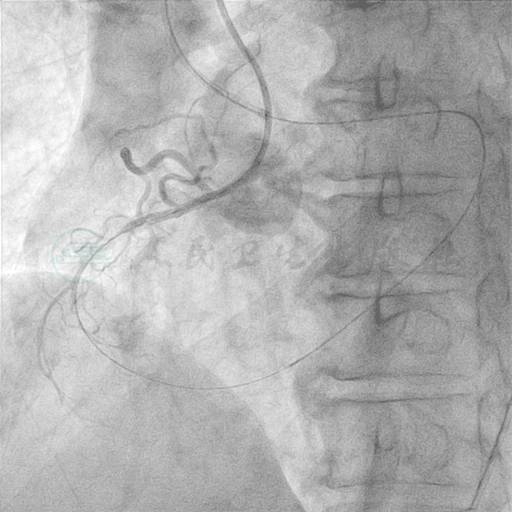

RCA-PCI过程。局麻下分别穿刺右侧股动脉及右侧桡动脉,沿超滑导丝分别送6F XBRCA导管至右冠口及6F XB-LAD 3.5导管至左冠口,双侧同时造影,明确RCA侧支循环中主支血管来自LCX中段。沿6F LAD 3.5指引导管送Fielder FC导丝至回旋支中段,沿侧支循环送入RCA远端,沿Fielder FC导丝送Finecross微导管至RCA远端(图14~图16),确认导丝位于RCA血管真腔内,继续前送Fielder FC导丝至RCA近段,并顺利送入前向指引导管,交换成300cm的Fielder FC,从导丝末端送入另一根Finecross微导管,反复尝试不能顺利通过病变狭窄段,交换成Sprinter1.5mm×15mm OTW球囊,仍不能顺利通过病变狭窄段,再送Corsair微导管,方顺利通过病变段至RCA远端。经微导管造影确认导丝位于RCA血管真腔内,撤出逆向Fielder FC导丝,沿6F XBRCA导管中的微导管送入BMW导丝至后降支远段,尾端接Extension延长导丝后,撤出Corsair微导管。造影证实逆向导丝沿途无明显并发症后,随即撤出逆向导丝和微导管。沿BMW导丝送Ryujin 1.5mm×20mm球囊,自RCA远段至近段以10~18atm扩张6次,造影管腔弥漫不规则狭窄,残余狭窄最重约90%,远端血流TIMI 3级,再使用Voyager NC 2.0mm×15mm球囊沿RCA远段至近段分别以8~10atm扩张6次(图17~图19),从后交叉前顺序植入Partner 2.75mm×29mm、3.0mm×29mm、3.0mm×29mm、3.5mm×29mm共4枚药物支架,复查造影示近段及中段支架扩张稍欠,送入Voyager NC 3.0mm×20mm球囊,在右冠中远段支架内后扩张,Voyager NC 3.75mm×15mm球囊,在右冠近段支架内后扩张,复查造影示支架扩张良好,无残余狭窄、内膜撕裂、夹层及远段血栓形成,TIMI血流3级(图20、图21)。撤导丝、导管,手术结束。

图14 双侧同时造影,明确RCA侧支循环中主支血管来自LCX中段

图15 沿6F LAD 3.5指引导管送Fielder FC导丝至回旋支中段

图16 沿侧支循环送入RCA远端,沿Fielder FC导丝送Finecross微导管至RCA远端

图17 Fielder FC导丝顺利送入前向指引导管,交换成300cm的Fielder FC,Corsair微导管通过病变段至RCA远端, 微导管造影确认导丝位于RCA血管真腔内

图18 撤出逆向导丝和微导管

图19 沿BMW导丝反复球囊扩张后,右冠造影示管腔弥漫不规则狭窄

图20 从后交叉前顺序植入Partner 2.75mm×29mm、3.0mm×29mm、3.0mm×29mm、3.5mm×29mm共4枚药物支架,复查造影示近段及中段支架扩张稍欠

图21 Voyager NC 3.0mm×20mm、Voyager NC 3.75mm×15mm球囊分别在右冠中、近段支架内后扩张,复查造影示支架扩张良好,无残余狭窄、内膜撕裂、夹层及远段血栓形成,TIMI血流3级